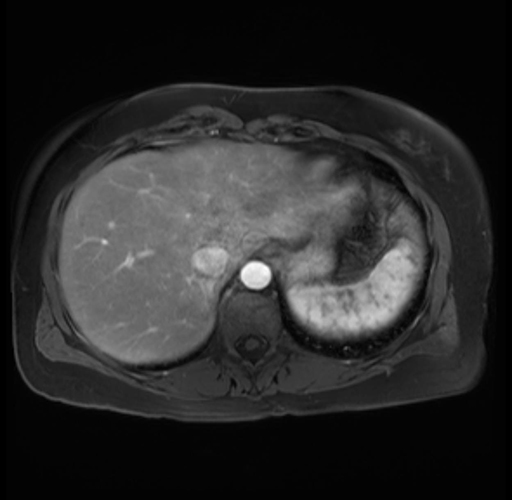

Imaging Analysis

Look through the patient's CT scan to identify any areas of concern for the necessary procedure.

Based on your CT findings, which issue(s) are present and would give reason for "planned slowing down moment(s)" in this case?